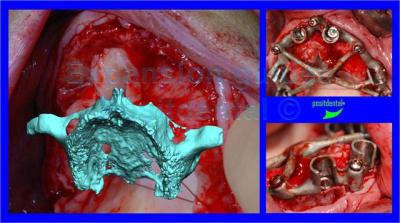

voici peut être une autre solution qui te satisfera d'avantage car beaucoup plus simple à mettre en œuvre.

c'est une simple ROG avec des vis pour maintenir l'espace sous la membrane.

13/12/2011 à 05h00

oups ! j'avais oublié les opt

merci à ceux qui ont déja pratiqué cette technique de me dire quel est leur mode opératoire. les résultats, les p'tits trucs pour faire avancer la science quoi ...

je trouve ça très intéressant, attendons la suite.

joli!

As-tu fait de l'ostéotension ou similaire pour augmenter l'apport sanguin ?

As-tu utiliser du PRF pour améliorer ostéoconduction?

comment as-tu obtenu la laxité gingivale pour fermer sans tension?

n'as-tu pas peur que malgré tout ça bouge avec la mastication?

Combien de temps laisses-tu cicatriser avant de réintervenir?